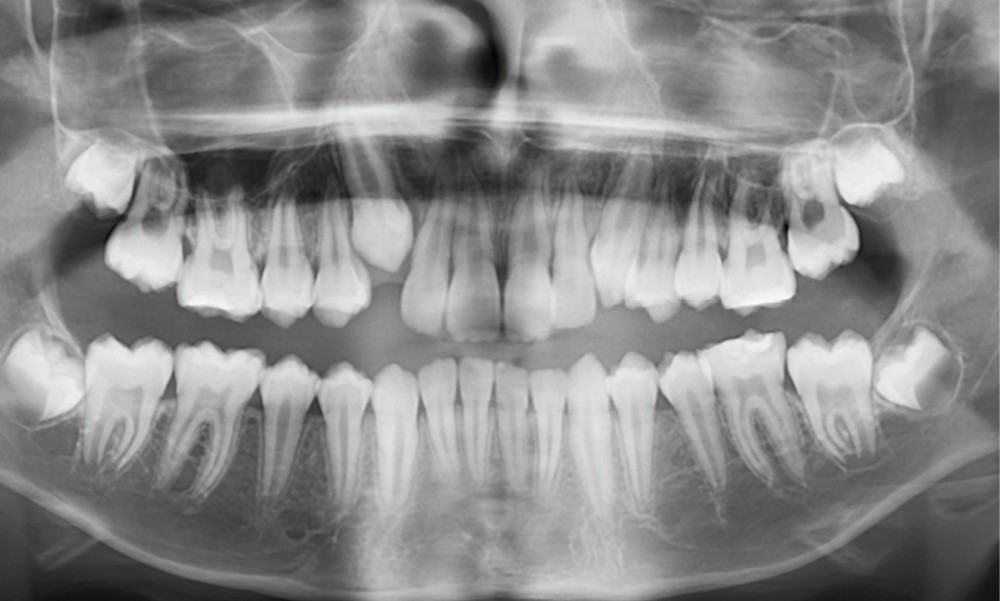

Fares, 13 ans, est adressé par son dentiste pour un bilan orthodontique dans le cadre d’une Hypominéralisation Molaire-Incisive (MIH). L’enfant est en bonne santé générale.

L’examen clinique montre une MIH sévère sur 16, 26, 36 et 46, et modérée sur 11 et 21.

Après concertation avec le service de pédodontie, un appareillage multi-attache bi-maxillaire est mis en place, associé à l’extraction des quatre premières molaires permanentes (16, 26, 36, 46).

Le moment de l’extraction est essentiel : à cet âge, les deuxièmes molaires n’ont pas terminé leur édification radiculaire, ce qui favorise leur mésialisation [2]. Néanmoins, la direction d’éruption, surtout mandibulaire, reste difficile à prévoir, et la présence des troisièmes molaires ne garantit pas leur éruption correcte [3].

Le choix d’extraction dépend de l’âge, du stade de développement des secondes molaires, de la présence des troisièmes molaires, de la DDA et des relations squelettiques.

L’extraction de 16, 26, 36, 46 a été réalisée 6 mois avant la pose du multi-attache, permettant une mésialisation spontanée partielle.